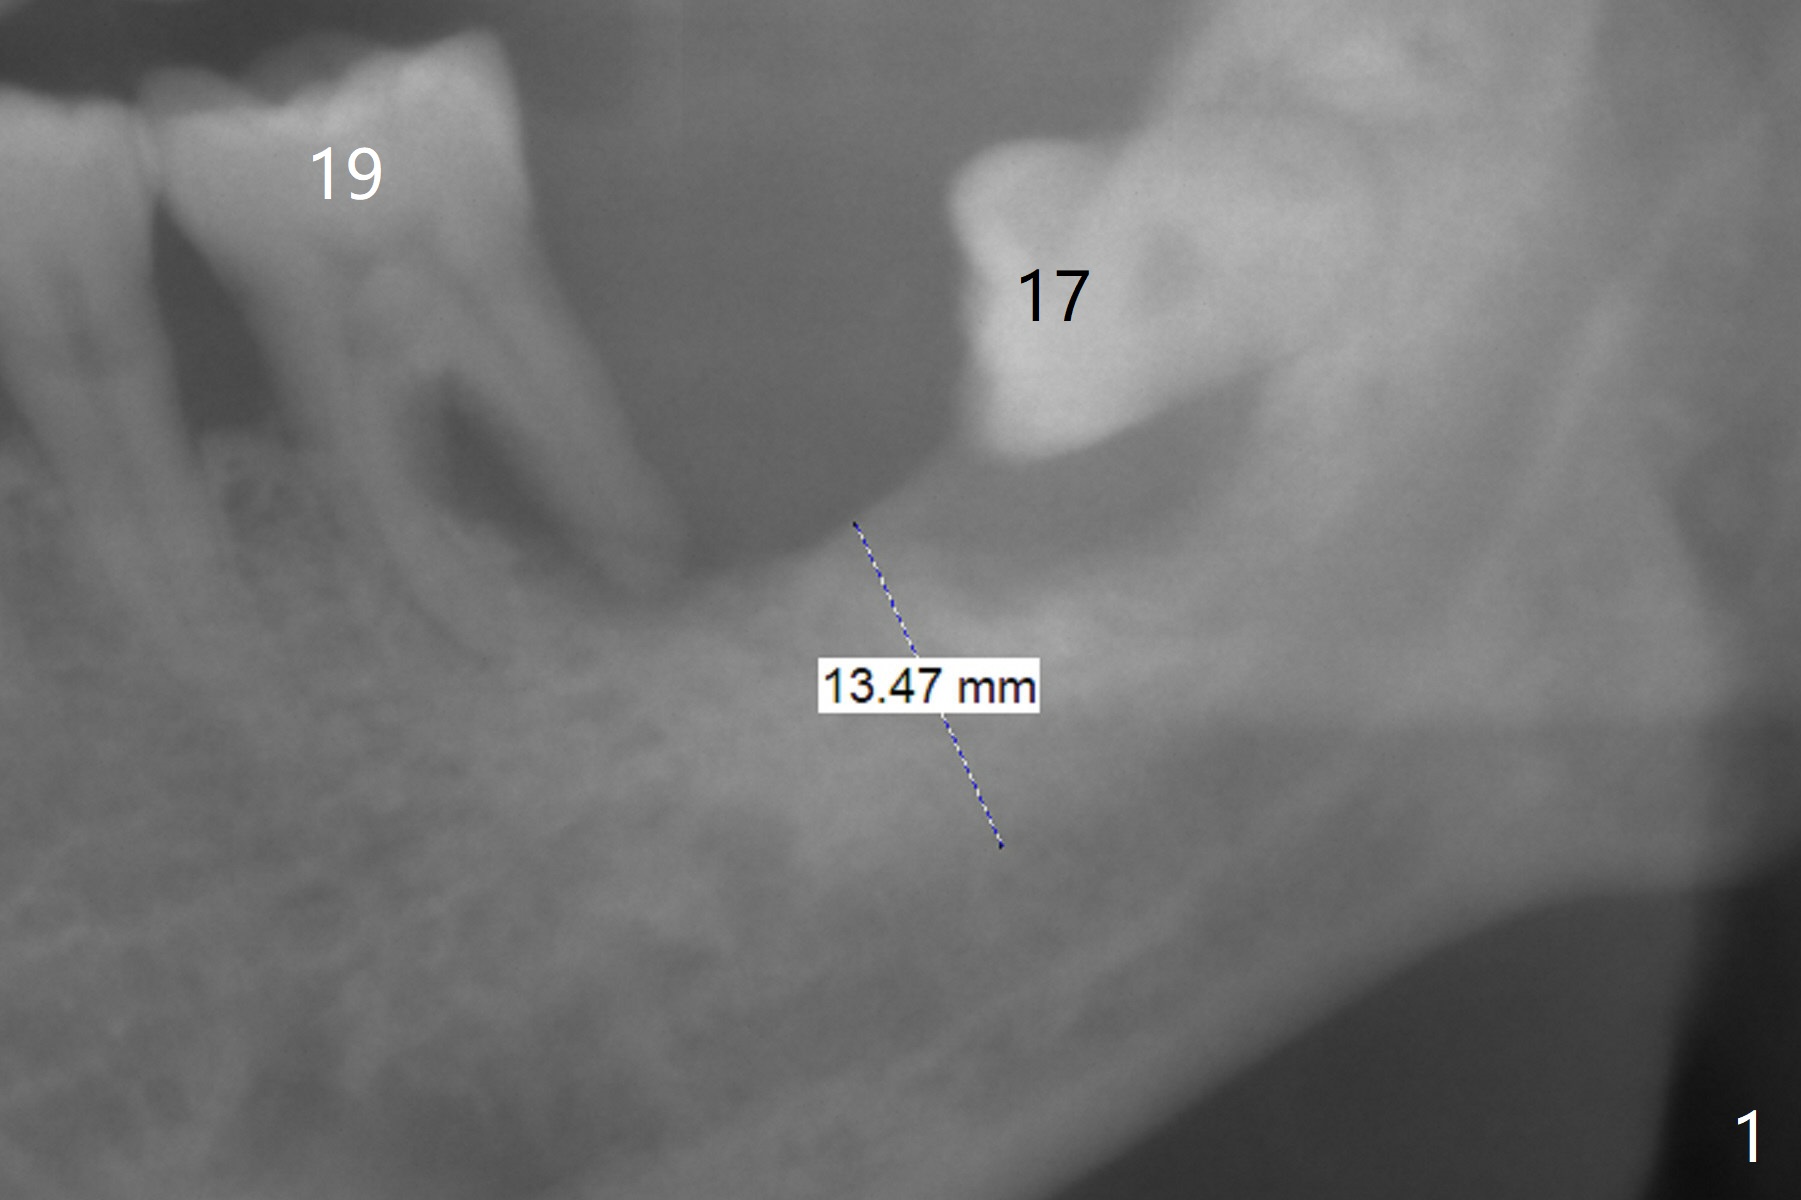

A 65-year-old man agrees to have an implant at #18 immediately after #17 extraction because of abutment screw loosening at #30. But the patient refuses #19 extraction. Since there is severe vertical bone loss at #18 (Fig.1), the implant should be as large as possible and tissue-level (Fig.2, 5 or 6x14 mm). The abutment is expected to be 5 mm long. After implant osteointegration, the abutment should be cemented with Panavia V5. To control infection at #19 temporarily, scale and place Arestin.